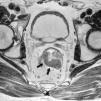

Grado de infiltración del tumorEn el diagnóstico por RM, cualquiera de las capas de la pared rectal se considera infiltrada en cualquier punto de su extensión cuando su intensidad de señal propia queda sustituida por la de la masa tumoral. Se describen varios estadios de infiltración según esta afecte a las diferentes capas del recto, mesorrecto u otras estructuras pélvicas. Un estadio T1 (fig. 2) implica la afectación de la mucosa y submucosa pero no así de la muscular, de manera que se conserva la hipointensidad de esta capa a lo largo de todo el anillo rectal, quedando la extensión del tumor por ella misma delimitada, sin ser invadida. Un estadio T2 (fig. 3) supone la afectación de la capa muscular, caso en el que su hipointensidad se pierde y se sustituye por la intensidad de señal del tumor, aunque conserva su contorno, sin infiltración en la grasa mesorrectal. Un estadio T3 (fig. 4) implica infiltración más allá de la muscular, por lo que el tumor se aprecia en la grasa como un frente redondeado o nodular3. La presencia de espiculaciones no es evidencia suficiente de infiltración3,4, ya que pueden estar causadas por fibrosis o por una inflamación peritumoral. Un estadio T4 (fig. 5) se da cuando la infiltración es de gran alcance y, rebasando la fascia mesorrectal, afecta a otras estructuras pélvicas, la hoja peritoneal (estadio T4a) o, una vez perforada esta, las vísceras intraperitoneales (estadio T4b).